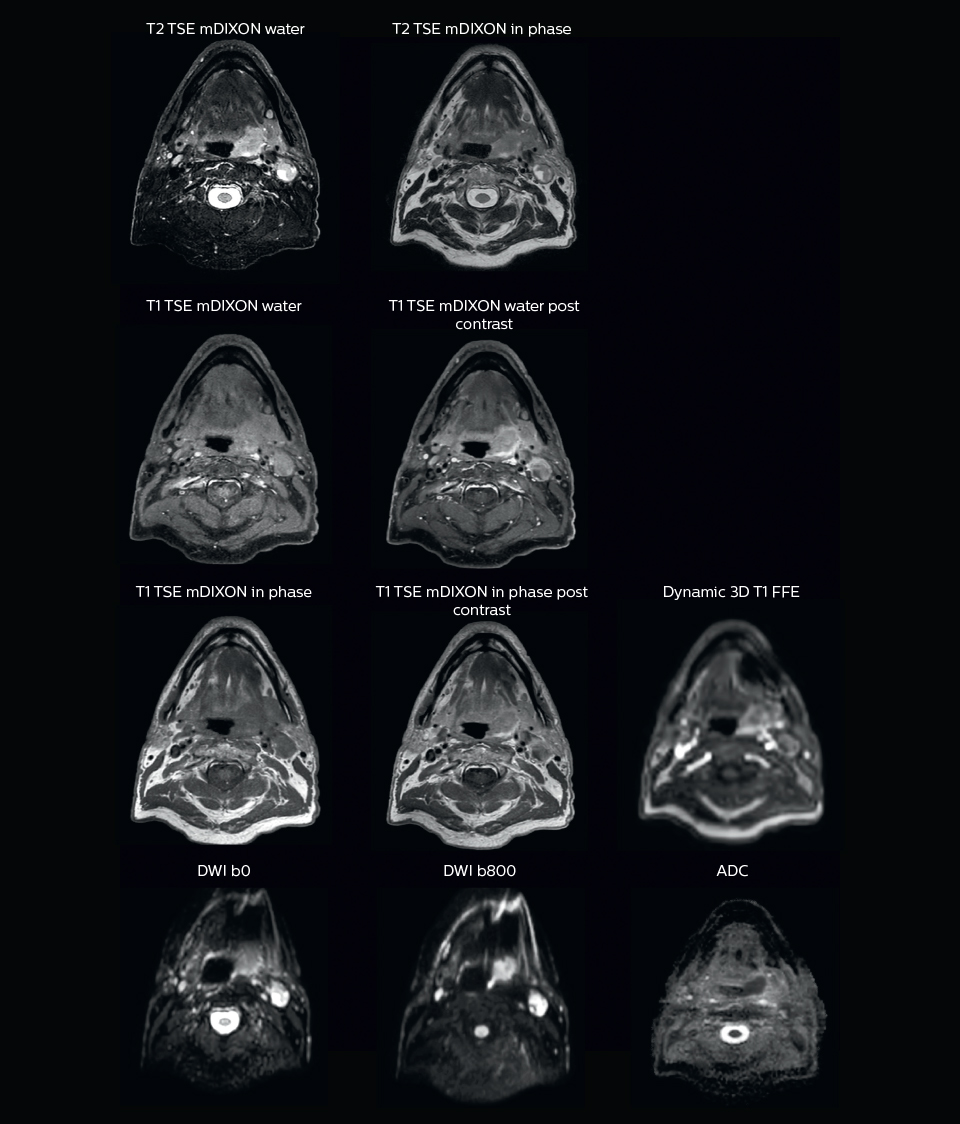

“When we can visualize intraprostatic lesions, the radiation therapist can then plan to boost them, giving a higher dose to those lesions instead of giving a uniform dose to the whole prostate, in the hope to better treat the patient and have less risk of recurrent tumors. However, this is not yet clinical routine. For visualizing the lesions, we not only use anatomical, T2-weighted imaging, but also diffusion weighted MRI and dynamic contrast- enhanced MRI."

A 63-year-old patient with prostate cancer, cT3bNxM, Gleason 7, underwent MRI on Ingenia 3.0T MR-RT before radiation therapy.

Intraprostatic lesions are visible on the bTFE MR image, but not on the CT image. MRI shows excellent soft-tissue contrast for the visualization of critical structures like the rectum and penile bulb.

“We use pre- and post-contrast T1- and T2-weighted sequences with the fast and robust mDIXON method for fat suppression,” says Dr. Philippens. “Dynamic contrast-enhanced imaging is performed with high temporal resolution and low spatial resolution, to see the contrast agent uptake in the tumor. Diffusion weighted imaging is used qualitatively to see how the tumor extends into another structure, rather than for strict delineation.”